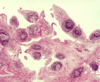

What will you see in joint effusions in an RA patient?

Neutrophils and Mononuclear cells